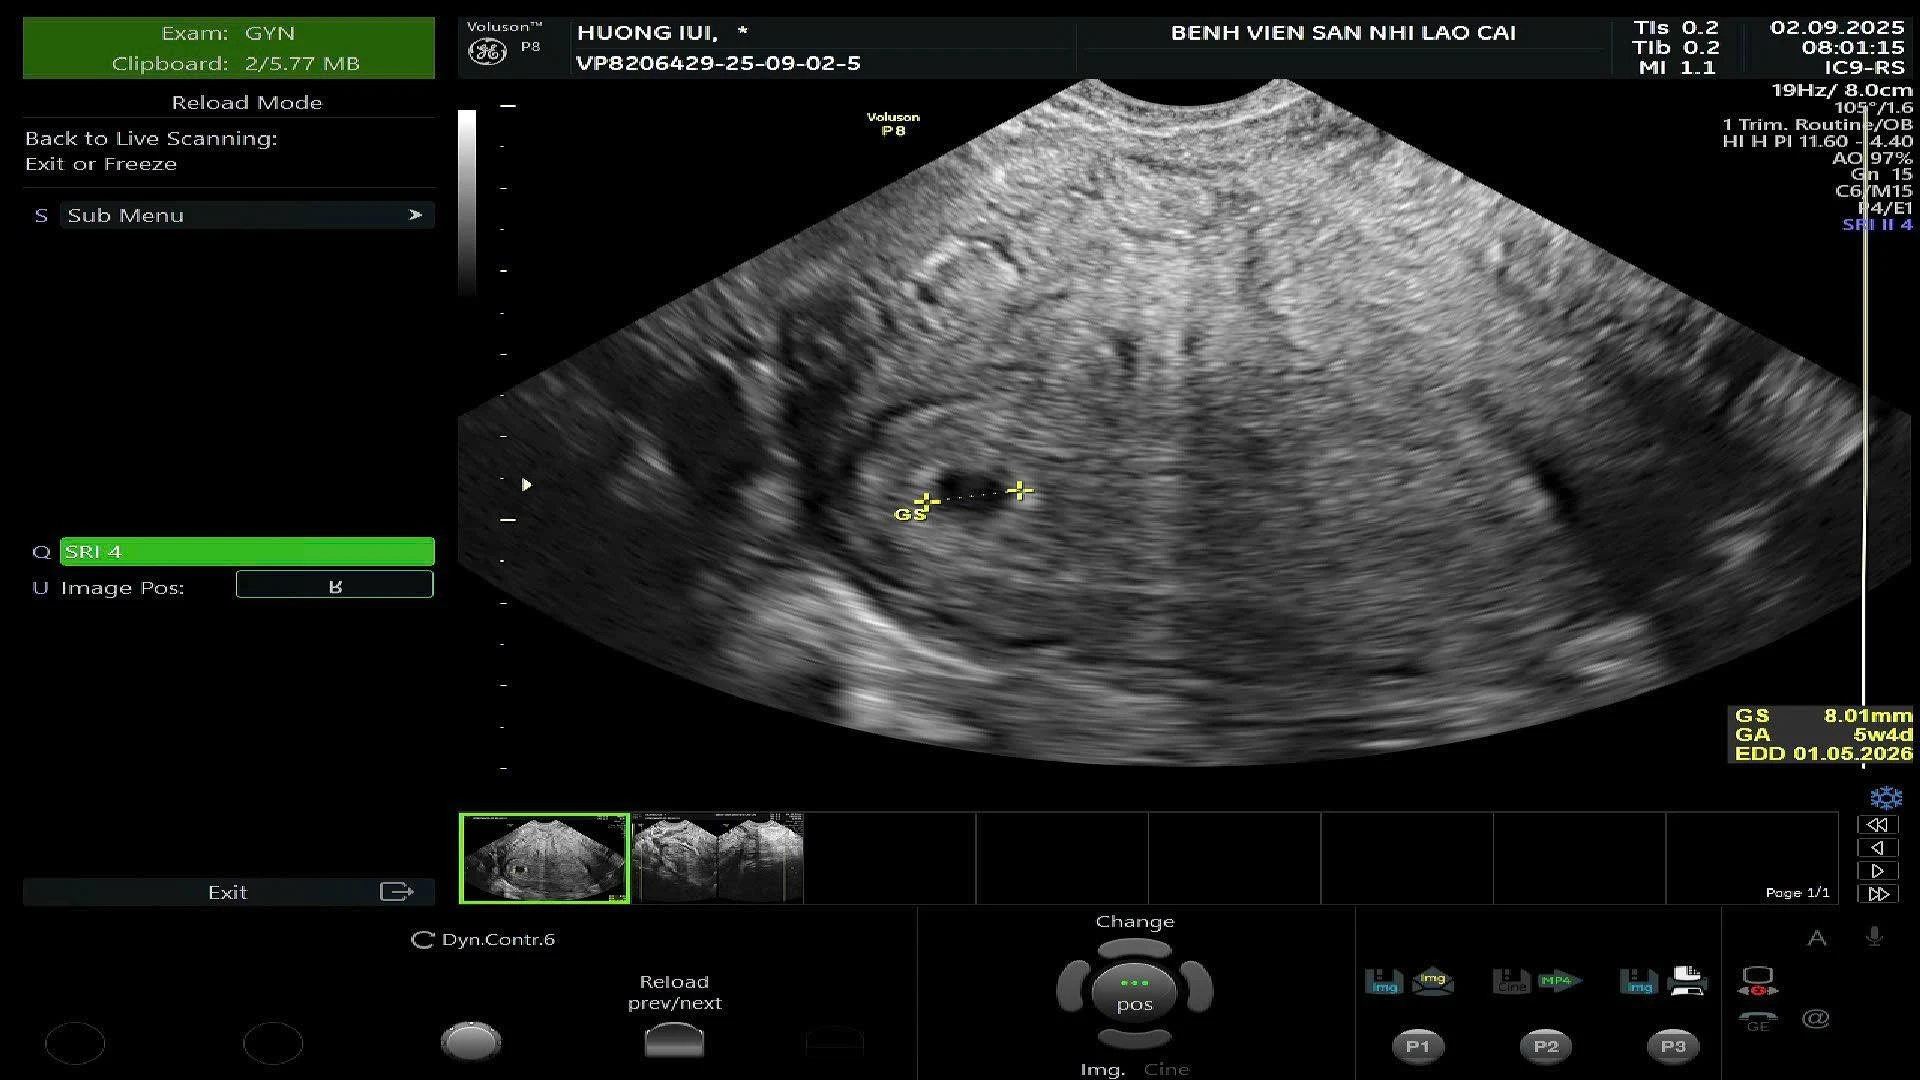

Ngày 10/9, Đoàn công tác Bệnh viện Sản - Nhi tỉnh Lào Cai đã thực hiện khảo sát, tư vấn triển khai kỹ thuật thụ tinh nhân tạo IUI tại Bệnh viện Đa khoa khu vực Mường Khương.

Tại buổi làm việc, Đoàn công tác của Bệnh viện Sản – Nhi tỉnh đã khảo sát cơ sở vật chất, trang thiết bị, trao đổi chuyên môn với đội ngũ bác sĩ, điều dưỡng của Bệnh viện Đa khoa khu vực Mường Khương và tư vấn quy trình triển khai kỹ thuật thụ tinh nhân tạo IUI an toàn, hiệu quả, góp phần triển khai dịch vụ hỗ trợ sinh sản tại đây.

Bệnh viện Đa khoa khu vực Mường Khương hiện đã cử bác sĩ đi đào tạo về kỹ thuật thụ tinh nhân tạo IUI. Triển khai kỹ thuật này tại Bệnh viện Đa khoa khu vực Mường Khương sẽ góp phần nâng cao chất lượng khám chữa bệnh, đáp ứng nhu cầu chăm sóc sức khỏe sinh sản ngày càng tăng của người dân; giúp người dân địa phương được tiếp cận dịch vụ y tế chuyên sâu, giảm bớt chi phí, thời gian đi lại lên tuyến trên.

Năm 2014, Bệnh viện Sản - Nhi tỉnh là bệnh viện đầu tiên trên địa bàn tỉnh thực hiện thành công phương pháp hỗ trợ sinh sản bằng thụ tinh nhân tạo. Kể từ đó đến nay, các bác sĩ đã mang lại niềm hạnh phúc cho nhiều cặp vợ chồng hiếm muộn.

Hỗ trợ sinh sản bằng thụ tinh nhân tạo IUI là phương pháp dùng ống nhỏ, đưa một lượng tinh trùng của người bố sau khi đã lọc rửa, chọn lọc con khỏe để bơm trực tiếp vào buồng tử cung của người mẹ.

Đây là phương pháp điều trị hiếm muộn dành cho các cặp vợ chồng có nhu cầu có con chủ động và được đánh giá là kỹ thuật hỗ trợ sinh sản an toàn, hiệu quả, tiết kiệm tối đa chi phí.